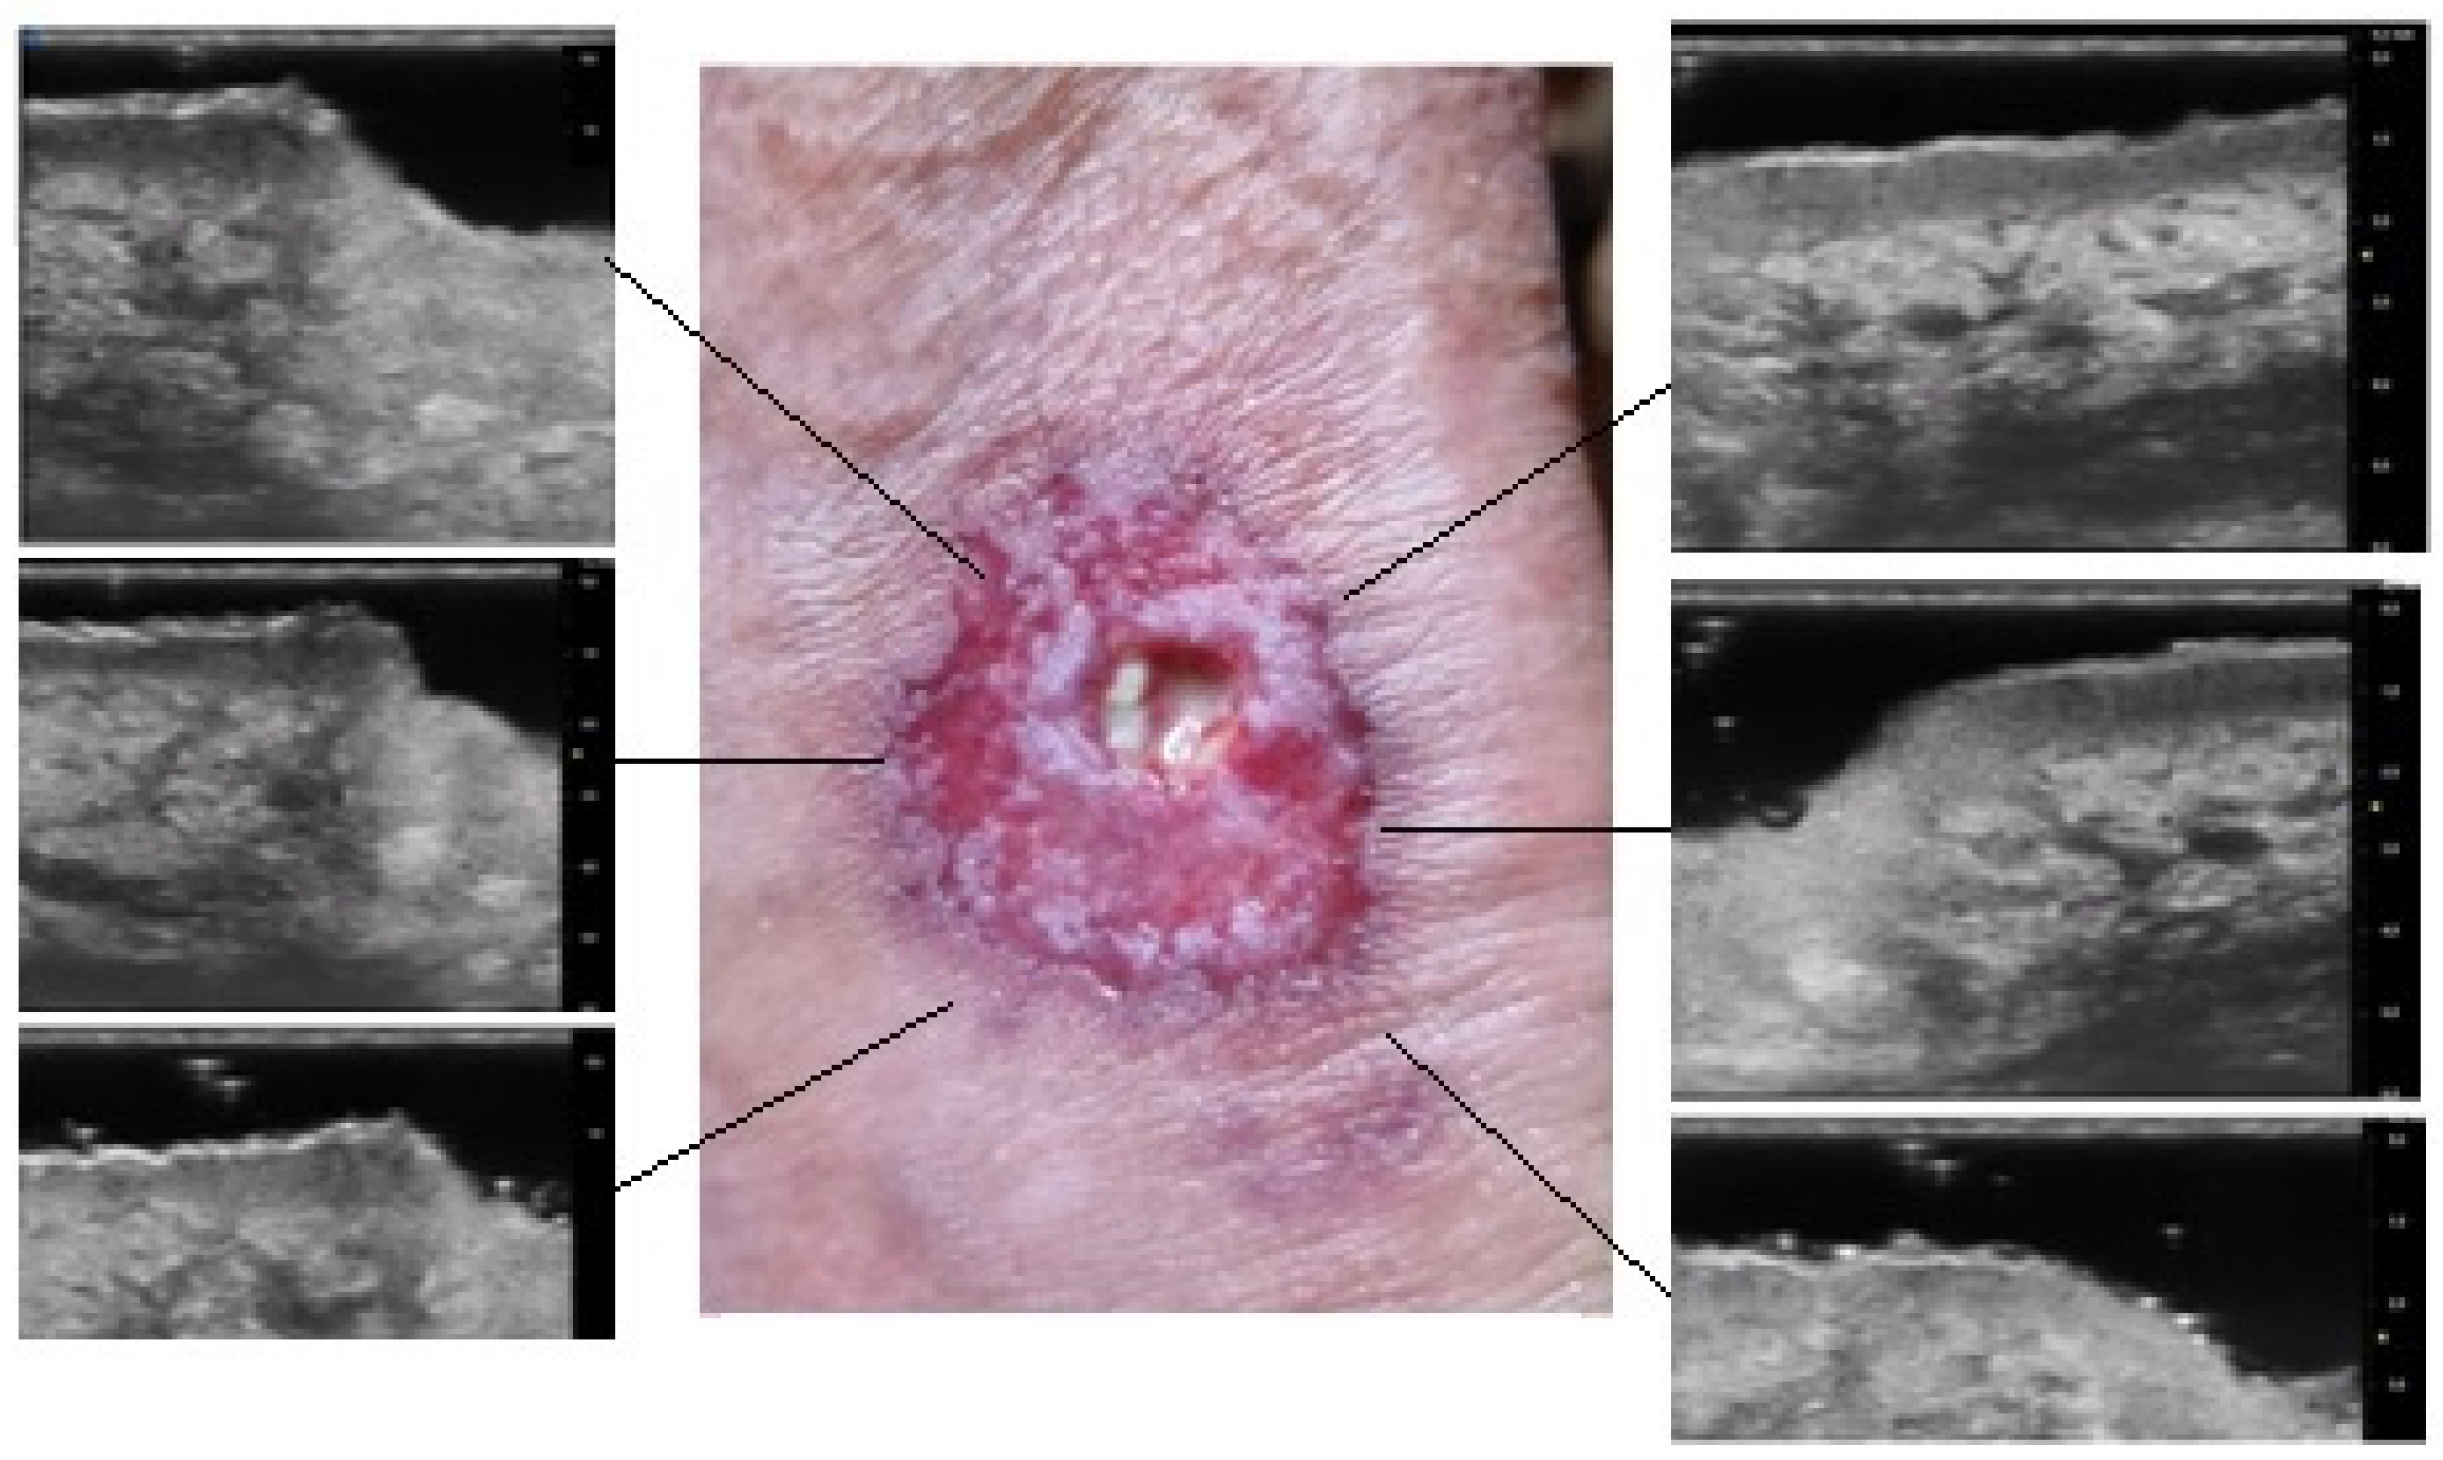

A comprehensive patient’s assessment was performed at T0 and T1. The clinical investigation was performed by a dermatologist expert in pyoderma gangrenosum which collected a photographic record of the patient and assessed clinical disease parameters such as pain, measured with VAS. UHFUS investigation was performed by a dermatologist expert in UHFUS blinded from the clinical diagnosis by three UHFUS clips with a 70 MHz linear probe (Vevo MD® FUJIFILM VisualSonics, Toronto, Ontario, Canada), in B-MODE. The use of UHFUS with a 70 MHz probe allows to examine the more superficial cutaneous and adnexal features with a spatial resolution in the order of 30 μm (Figure 1). A correlation between digital photograph and US clip was performed: two regions of interest (ROI) at the wound bed and edge were provided for the ulcerative phenotype, while one ROI was provided for the pustular phenotype. The probe was placed perpendicular to the lesion and a large amount of gel was used to maintain the adequate distance from the skin surface. The US parameters (such as gains, depth, time gain control, focus) were optimized during the examinations. A qualitative-quantitative analysis of the US features was performed by 2 dermatologists experienced in UHFUS imaging.

The results obtained by our investigation revealed some UHFUS differences between the inflammatory and non-inflammatory phases. At T0, oval hyperechoic structures, that statistically significantly decreased in T1, were identified in the papillary and reticular dermis (p-value < 0.05) (Figure 4 and Figure 5).

Figure 4. Patient affected by ulcerative Pyoderma Gangrenosum (PG) of the calf during the inflammatory phase: clinical aspect of the wound and its Ultra-High Frequency UltraSound (UHFUS) correlates.